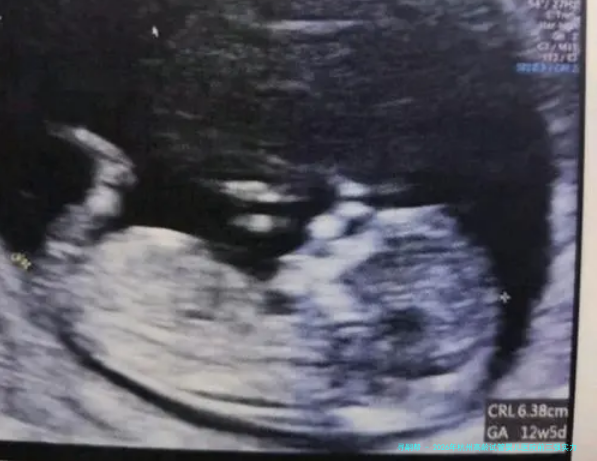

患者真实评价:“我系四十四岁在这里做的三代试管,1次成功。感觉这里的实验室技术真的很强,医生给方案也很果断,没让我走弯路。即是人过多了,排队有些艰苦。”